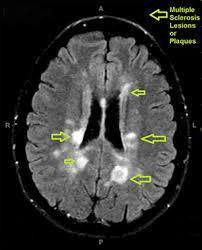

MRI findings in multiple sclerosis

Periventricular plaques (areas of oligodendrocyte loss and reactive gliosis)